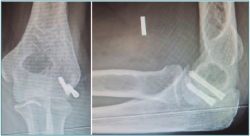

Las fracturas I y II pueden tratarse con una técnica asistida por artroscopia mediante una reducción cerrada, fijación inicial con 1 AK y fijación retrógrada con el uso de 1-2 tornillos canulados (Figuras 3 a 6).

Figura 4. Fractura de capitellum: colocación de 2 tornillos canulados.

Figura 5. Control radiográfico de fractura de capitellum asistida por artroscopia.